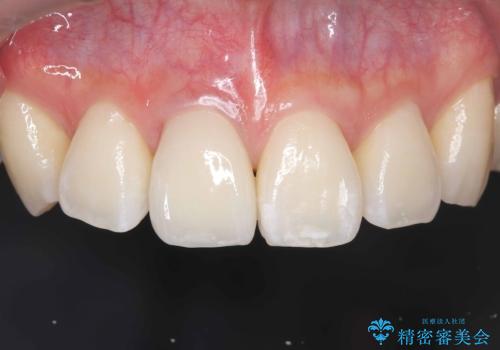

根管の充填物も不十分だったため根管治療からやり直しオールセラミッククラウンで治療を行いました。

根管の中が空洞のままで被せ物と歯のきわも合っておらず適合が悪い状態でした。根尖部付近にはパーフォレーションリペア修復の痕がありました。バイオシーシーラーを使用しシングルポイント法で充填しました。空洞があると細菌が増える環境になってしまうので、根管治療からやり直し、緊密に充填しました。被せ物の見た目も大変満足していただけました。